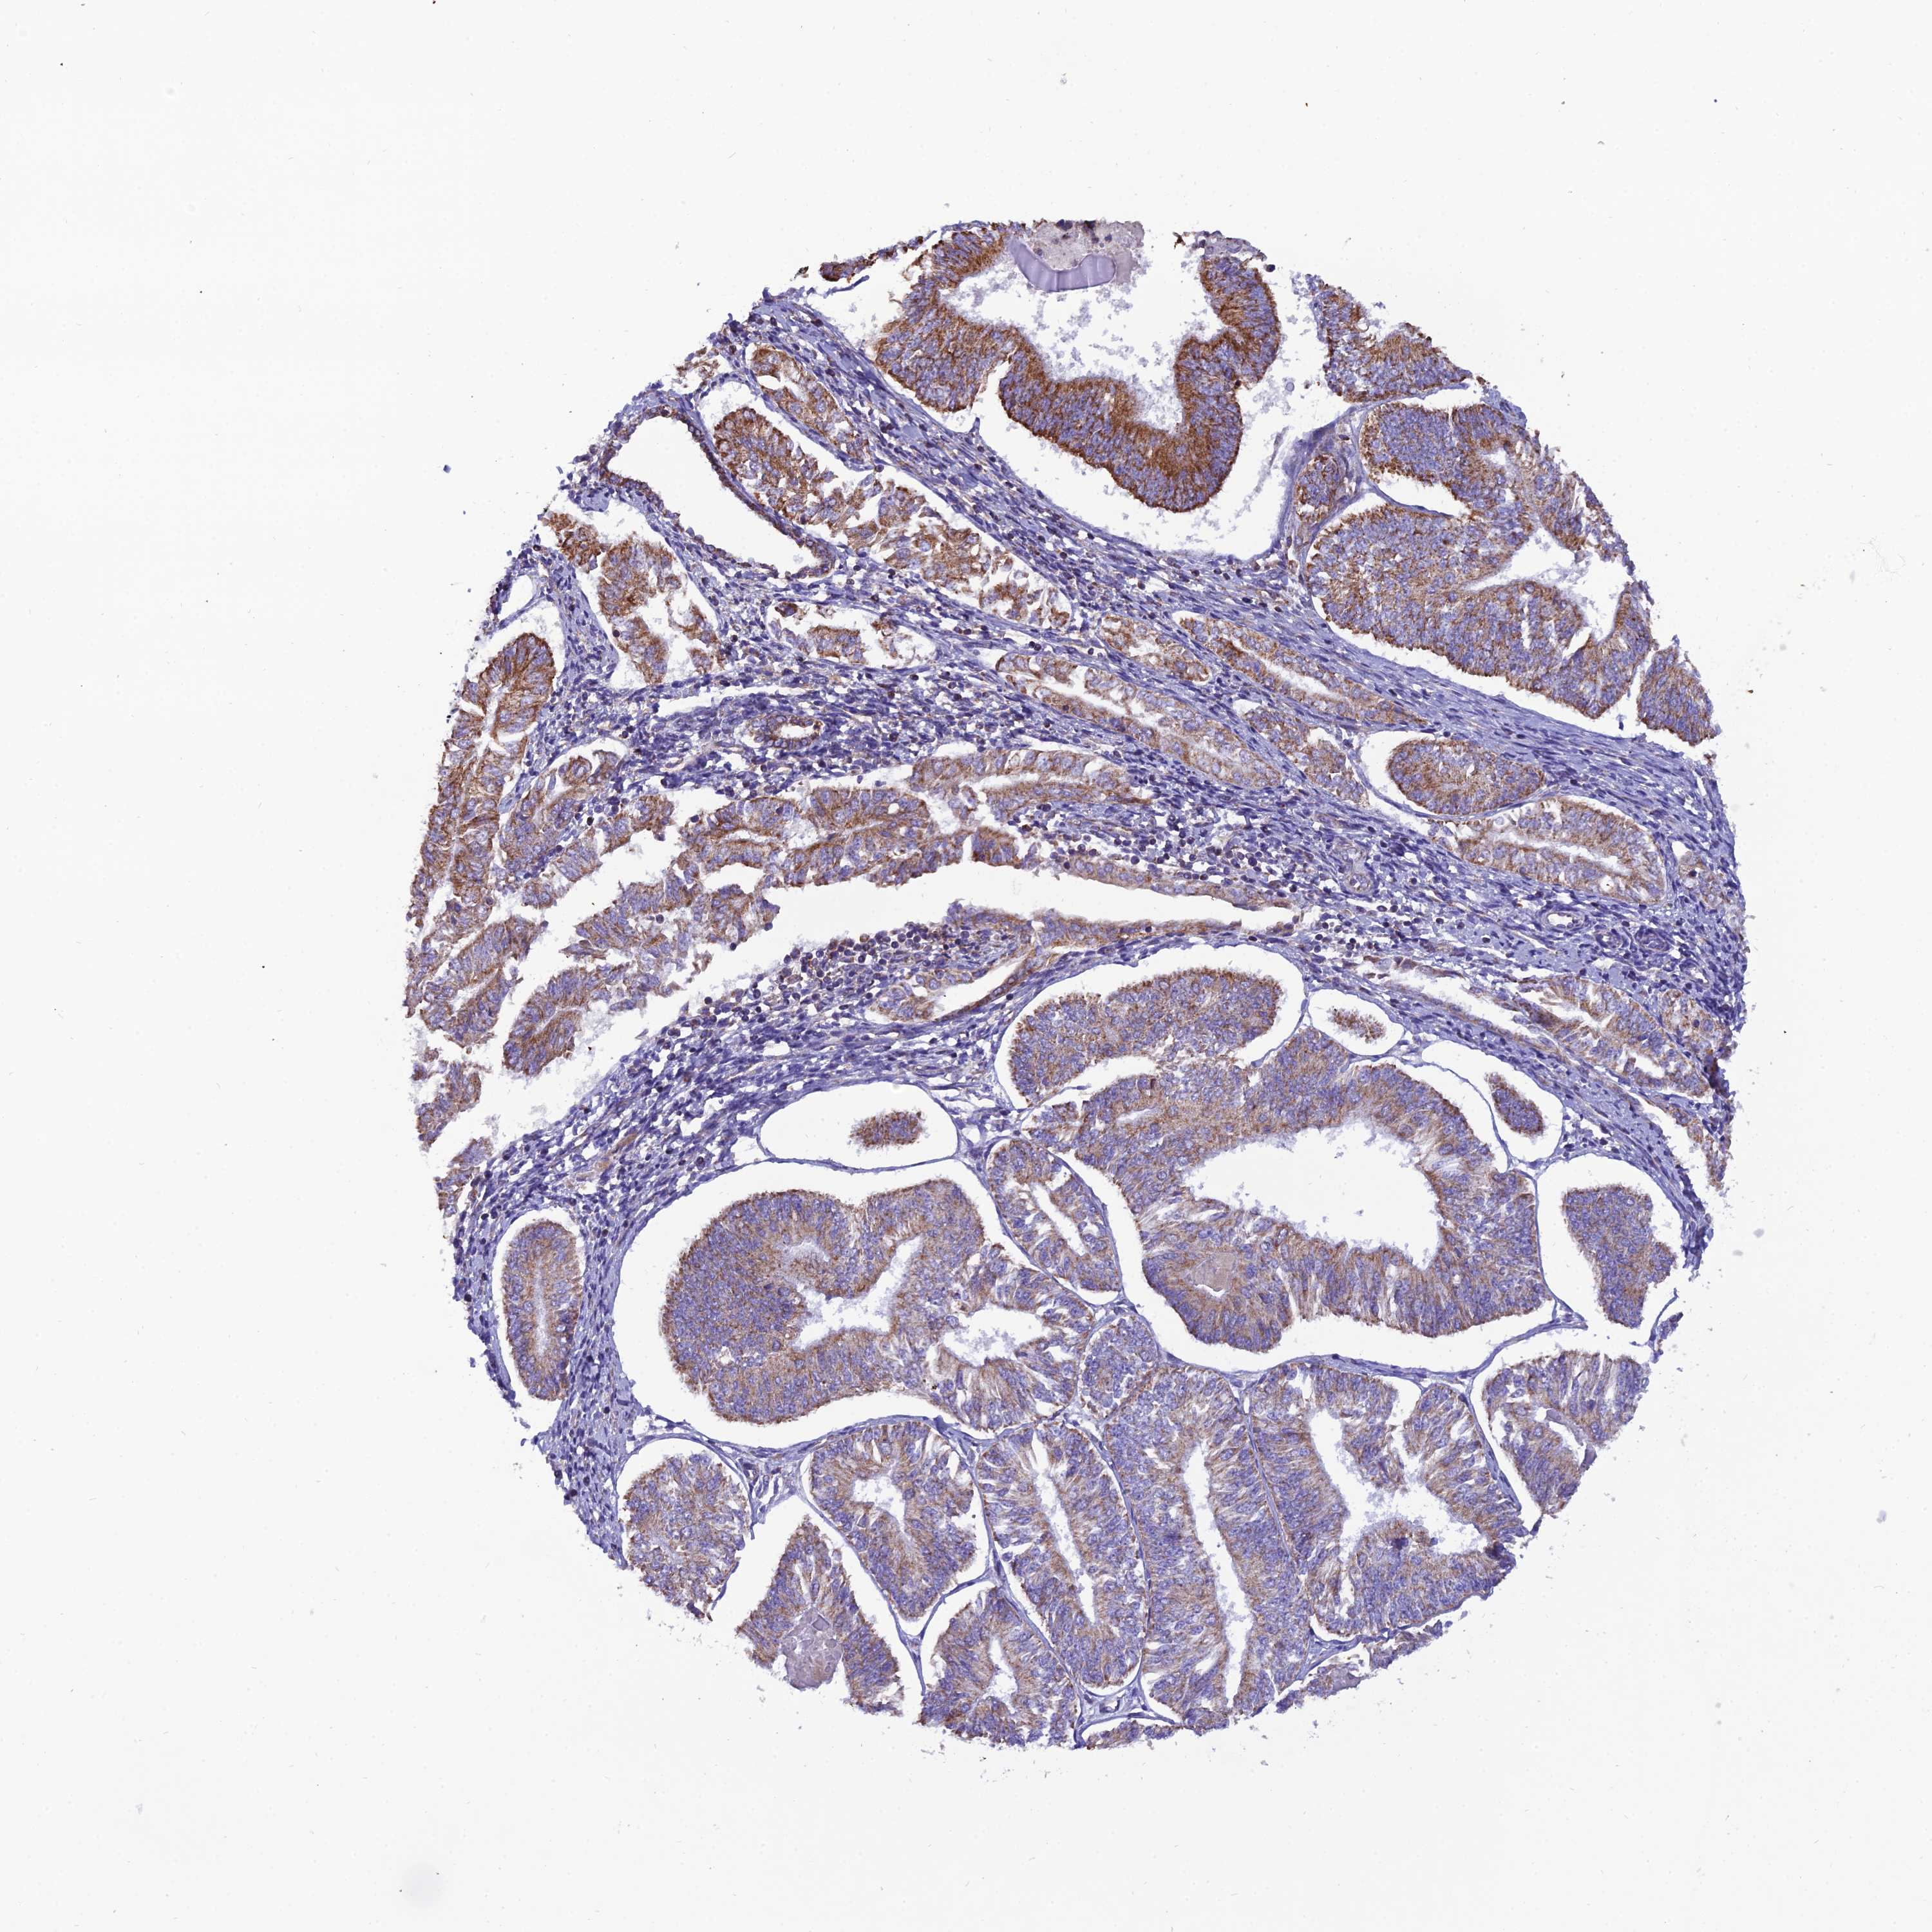

ENDOMETRIAL CANCER - Protein expressioni

A mouse-over function shows sample information and annotation data. Click on an image to view it in a full screen mode. Samples can be filtered based on level of antibody staining by selecting one or several of the following categories: high, medium, low and not detected. The assay and annotation is described here.

Note that samples used for immunohistochemistry by the Human Protein Atlas do not correspond to samples in the TCGA dataset.

Antibody stainingi

Antibody staining in the annotated cell types in the current human tissue is reported as not detected, low, medium, or high, based on conventional immunohistochemistry profiling in selected tissues. This score is based on the combination of the staining intensity and fraction of stained cells.

Each image is clickable and will lead to virtual microscopy that enables deeper exploration of all samples and also displays staining intensity scores, fraction scores and subcellular localization as well as patient and tissue information for each sample.

Antibody HPA044620

Antibody HPA058621

Staining

High

Medium

Low

Not detected

Intensity

Strong

Moderate

Weak

Negative

Quantity

>75%

75%-25%

<25%

None

Location

Nuclear

Cytoplasmic/membranous

Cytoplasmic/membranous,nuclear

Adenocarcinoma, NOS